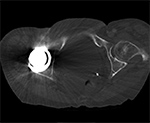

Figure 3A Figure 3B Figure 4A Figure 4B

Artifact summation Artifact summation Windowing Windowing

Artifact Summation. (A) Scout image demonstrates bilateral total hip arthroplasties. (B) Axial CT image at the level of acetabular cup and femoral head shows severe transverse streaking related to total summed attenuation of metal components. Optimal Windowing. (A) Axial CT image of the pelvis viewed in soft tissue windows demonstrates extensive streak artifact due to total hip arthroplasty prohibiting evaluation of adjacent bone and soft tissue structure. (B) Same axial CT image set to bone windows results in improved visibility of adjacent bone and soft tissue anatomy.